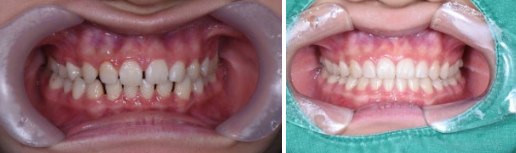

치아교정 전후 비교

초진에서는 파노라마 엑스레이와 구강 상태 확인 후 대략적인 치료 방향을 안내받고, 정밀검사에서 자세한 기록을 만들어 치료 계획을 확정합니다.

처음 방문하는 초진에서는 치아와 턱 주변을 넓게 촬영하는 파노라마 엑스레이와 구강 상태 확인을 통해,

교정적으로 어떤 문제가 있는지 파악하고 대략적인 치료 방법을 설명드립니다.